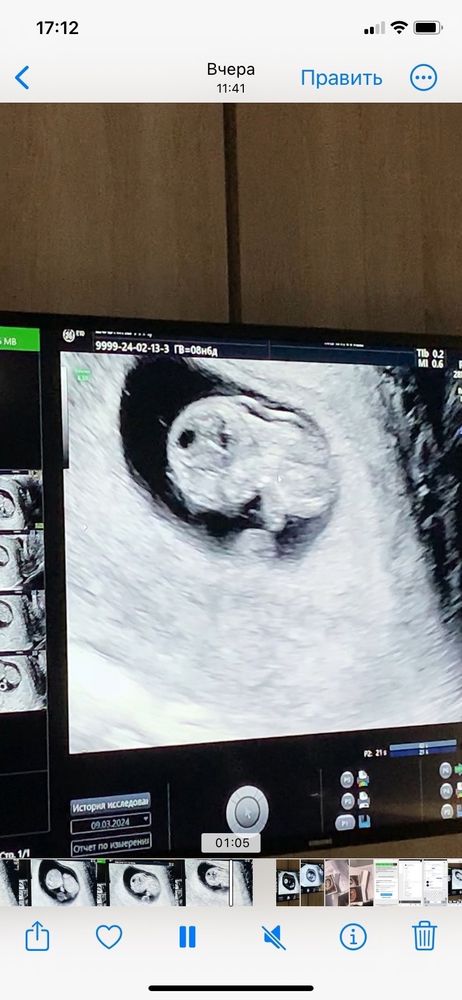

Узи 9 недель

Не паникуйте. Не понимаю врача, которая Вас напугала на таком сроке. ТВП измеряется ТОЛЬКО сроке 12 недель, т.е. на первом скрининга. Также ТВП смотрят вместе с КТР, если уже ТВП больше 3 будет на скрининге, тогда уже стоит дальше обследоваться и искать причину. Сейчас Вам просто бессмысленно измерили ТВП и напугали, успокойтесь и ждите скрининга. Хорошей беременности🌸

А какое твп?

Юлия, в том то и беда, что она его не измерила, сказала, что сейчас измерять будет нечестно и некорректно вроде бы. Я ей тем же вечером написала в социальной сети, она также ответила мне, хотя я просто спросила увеличено оно или нет